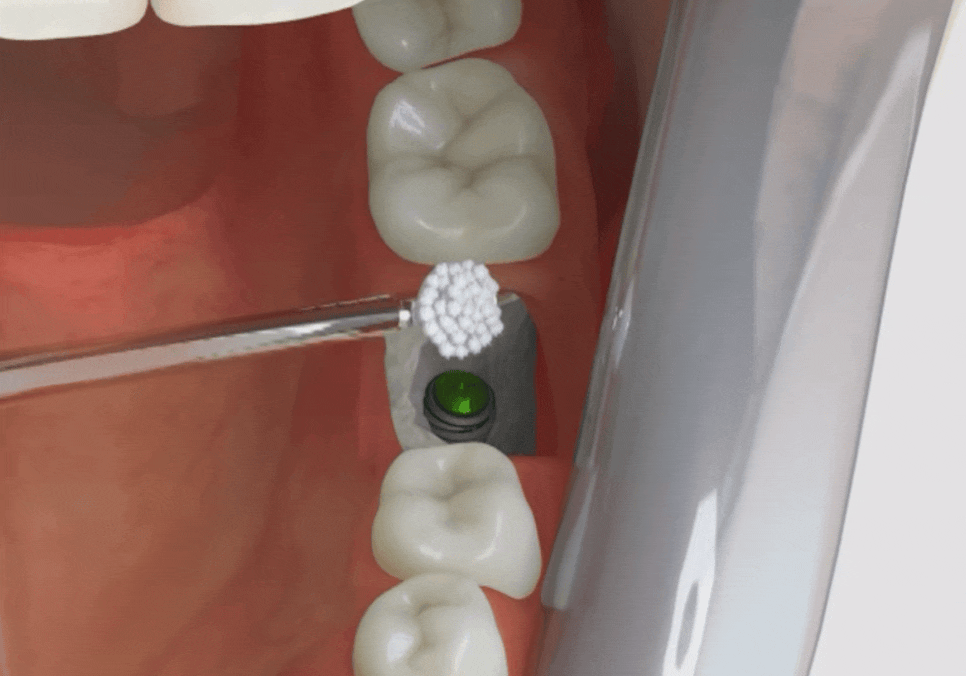

임플란트와 뼈이식, 3개월의 기다림

강동구 치아 뿌리 염증, 신경치료 한 치아인데도 아플 수 있나요?

염증 때문에 녹아버린

잇몸 뼈를 보충하기 위해

임플란트 식립과 동시에

뼈이식을 함께 진행했습니다.

뼈이식은 마치 영양분이 다 빠져나간

푸석푸석한 흙에 기름진 새 흙을

듬뿍 섞어주는 과정이라고

생각하시면 이해가 빠르실 것 같아요.

그래야 임플란트라는 나무가

흔들림 없이 튼튼하게 자리를 잡고,

수십 년을 써도 끄떡없는

단단한 기초가 만들어지기 때문이죠.

기초 공사가 튼튼해야 그 위에

올라가는 보철물도 오래도록 내 치아처럼

편안하게 사용하실 수 있답니다.^^